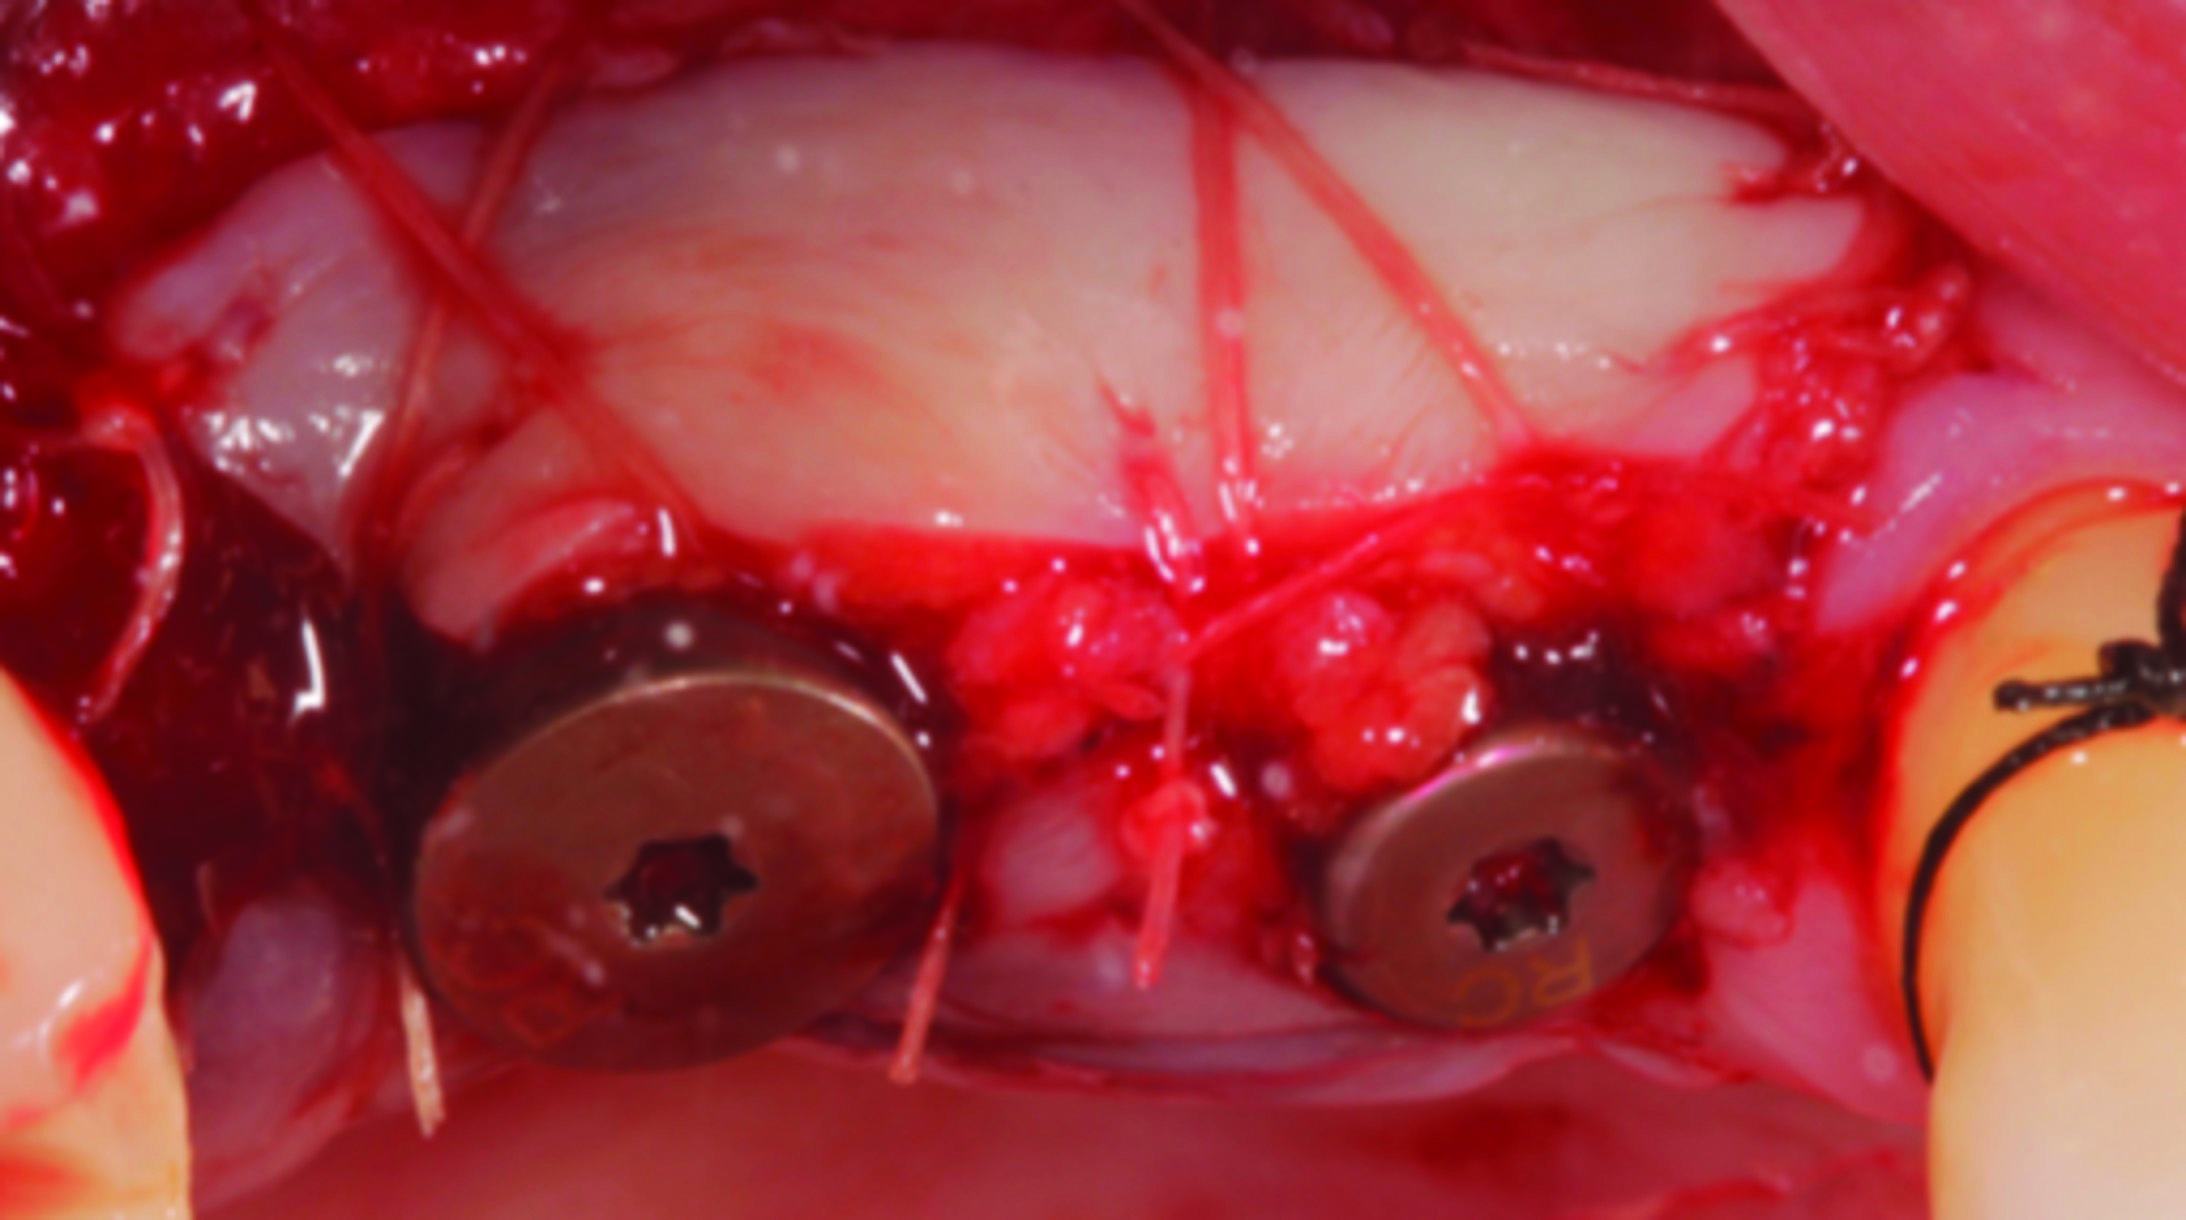

Fig 12 through Fig 14. Example of increasing MT with a roll technique. Fig 12: incision design for implant placement with a healing abutment placement and to enhance MT; the recipient site is prepared on the buccal side; the palatal aspect of the flap will be rolled to the buccal recipient site; Fig 13: insertion of roll of tissue taken from the palatal aspect of the flap; Fig 14: implant placement with healing abutment.

Figure 12

Figure 13

Figure 14